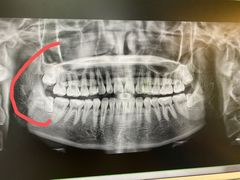

• 华颜美口腔矫正·种植牙

• -华颜美口腔矫正·种植牙